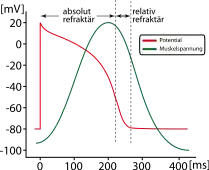

| Response to stimulus |  |

|

|